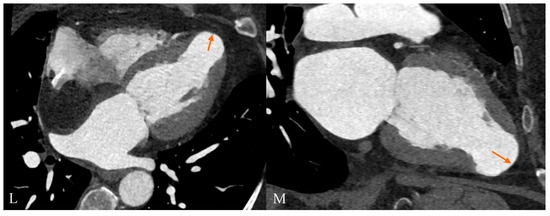

Cardiac Computed Tomography as a Method of Diagnosing the Type of Cardiac Tumor—Example of Interatrial Septal Lipoma Filling the Right Atrium

Gać, P.; Jaworski, A.; Parfianowicz, A.; Surma, A.; Jakubowska-Martyniuk, A.; Żórawik, A.; Poręba, R. Cardiac Computed Tomography as a Method of Diagnosing the Type of Cardiac Tumor—Example of Interatrial Septal Lipoma Filling the Right Atrium. Diagnostics 2024, 14, 2496. https://doi.org/10.3390/diagnostics14222496